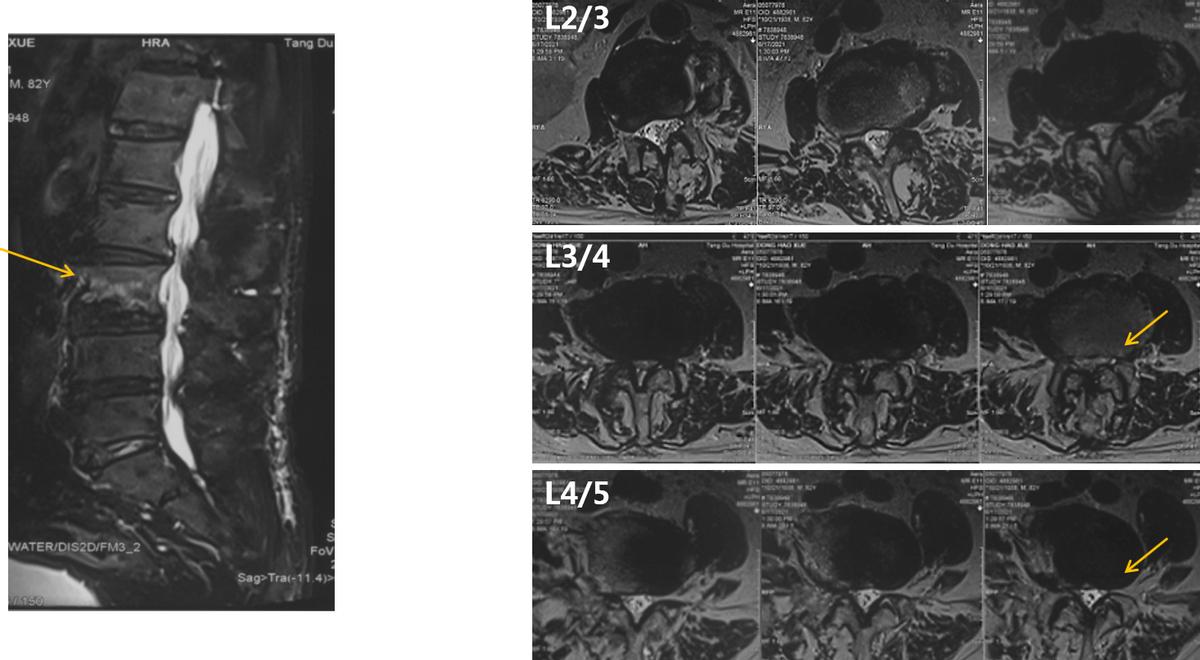

而从患者的核磁共振上可以观察到,腰3出现压缩性骨折,并且腰椎管出现狭窄。

MRI

由于患者Cobb角在30°左右,廖博主任团队决定进行“责任节段+X”短节段固定。为了精确责任节段,给患者进行了L5神经根选择性阻滞,原有症状没有诱发和缓解。因此,排除L4/5,将责任节段明确定位到L3/4。最终治疗方案决定为进行 L3/4的TLIF手术,钉道强化,L3椎体强化,术后进行长期的抗骨质疏松治疗。